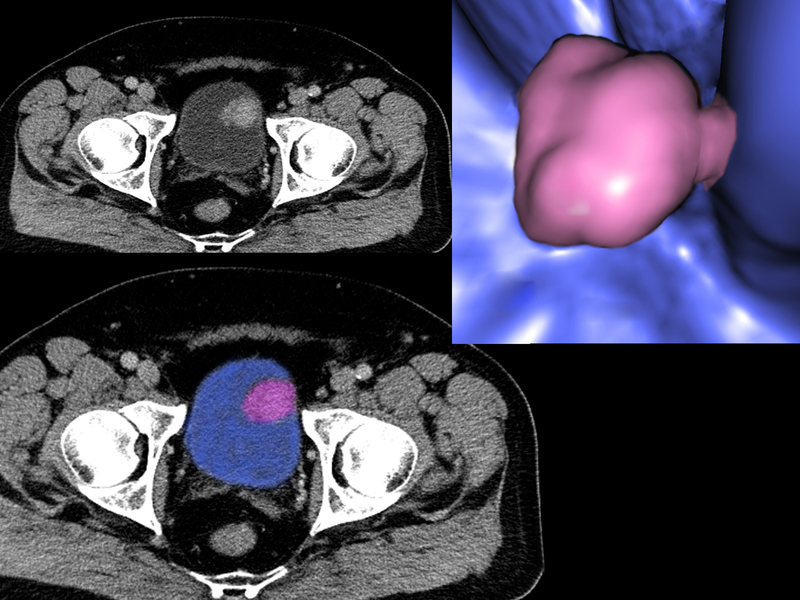

Experiencing menopause before the age of 45 is associated with a higher risk of bladder cancer particularly among smokers, says a new study.

Women who entered menopause before the age of 45 were 45 per cent more likely to have bladder cancer than those who had menopause after 50. However, if these women had smoked, the risk of bladder cancer was 53 per cent greater than women who had menopause later, the researchers said. "We found that smoking women who experienced menopause before they were 45 years old had a greater risk of bladder cancer. Smoking remains the most important risk factor for bladder cancer," said lead researcher Mohammad Abufaraj at the University of Vienna.

In general, around three times more men than women get bladder cancer, but the mortality rate in women is around 40 per cent higher. Delay in diagnosis, genetic or epigenetic factors and hormonal factors could be some of the reasons for these differences. However, the study "revealed that it is unlikely that factors such as age when periods begin, number of pregnancies, oral contraceptive use or the use of hormone replacement therapy are associated with bladder cancer risk", Abufaraj added. For the study, the team examined health outcomes of more than 220,000 nurses.